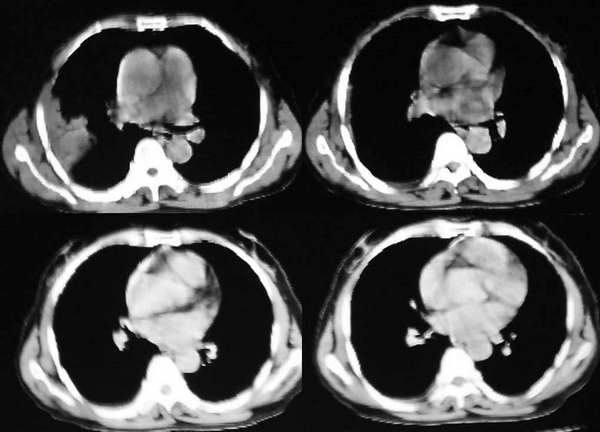

咳嗽10多天,畏寒,发热3天,

右肺大片状阴影,边缘模糊,其内见充气支气管征。肺门结构正常。支持肺炎性病变。

右肺上叶尖后段大片扇形实变影,密度较均匀,内见支气管空气造影征,气管腔静脉间淋巴结稍大呈小结节影,结合临床考虑大叶性肺炎。

右肺上叶尖后段大片扇形实变影,边缘略呈云片状渗出。并见“支气管气相”,结合病史支持大叶性肺炎诊断。建议正规抗炎复查。

右肺大片云片状渗出性阴影,边缘模糊,扇形分布其内见充气支气管征,肺纵比率<50%,结合病史支持大叶性肺炎诊断。

右上叶后段见大片状实变阴影,见含气支气管征,近肺门见支气管血管束增粗,上腔静脉后见小淋巴结. 后胸膜腔见少量积液. 印象:1,大叶性肺炎.2,节段性肺炎<混合菌感染>.3.建议抗炎后复查待除外其他病变

右肺上叶肺实变,内见①支气管气像②边缘模糊③叶间裂稍饱满这些都是支持肺炎的证据。尤其是边缘模糊,其病理学依据是炎症渗出性物质通过肺泡间孔和/或呼吸性细支气管向临近的肺组织蔓延渗透,和其他表现在一起成为诊断肺炎的重要表现。